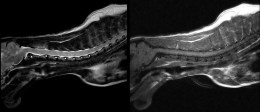

Деталізований знімок шийного відділу хребта кота у сагітальній проекції: чітка візуалізація спинного мозку та міжхребцевих просторів

Покращена візуалізація патологій

Система забезпечує високу діагностичну ефективність при виявленні дегенеративних змін міжхребцевих дисків, пухлинних процесів та запальних захворювань центральної нервової системи